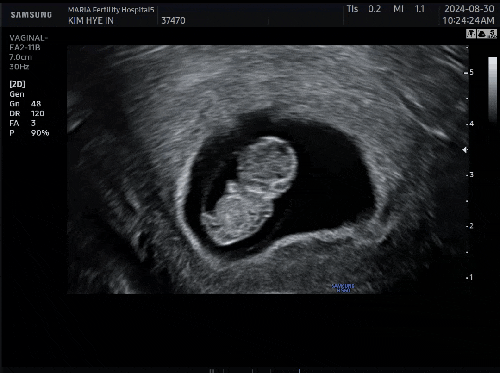

임신 9주차 마리아 졸업

미니미프로젝트 임신 9주차 마리아 졸업 유난히 하늘이 높고 맑았던 날, 선선한 바람까지 불어와 괜히 기분...